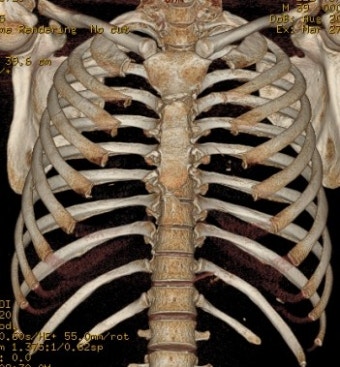

갈비뼈 골절은 늑골(갈비뼈)이 충격으로 인해 금이 가거나 부러진 상태를 말합니다. 우리 몸의 흉곽은 비교적 단단하지만, 예상치 못한 강한 힘을 받게 되면 골절이 발생할 수 있습니다.

전문의의 X-ray 또는 CT 진단을 통해 결정됩니다.